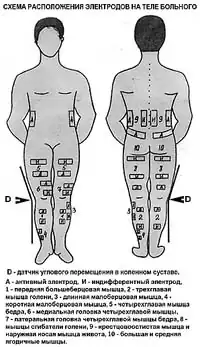

Многоканальная электромиостимуляция

Многоканальная электромиостимуляция (МЭСМ) применяется у больных, в том числе старших возрастных групп, с выраженными нарушениями функции мышц и двигательного стереотипа с применением 6-канального стационарного электростимулятора под клинико-биомехано-электромиографическим контролем. Этот метод сочетается с мышечными, проводниковыми, внутрикостными блокадами, со внутрисуставной инъекционной терапией и электромиостимуляцией в покое. Положительный эффект лечения возможен, если при мануальном тестировании сила мышц составляет не менее 2 баллов. Кроме того, непременным условием проведения процедуры является возможность самостоятельного передвижения больного с дополнительной опорой или без неё на расстояние не менее 10 метров, а также отсутствие резко выраженного болевого синдрома[46].